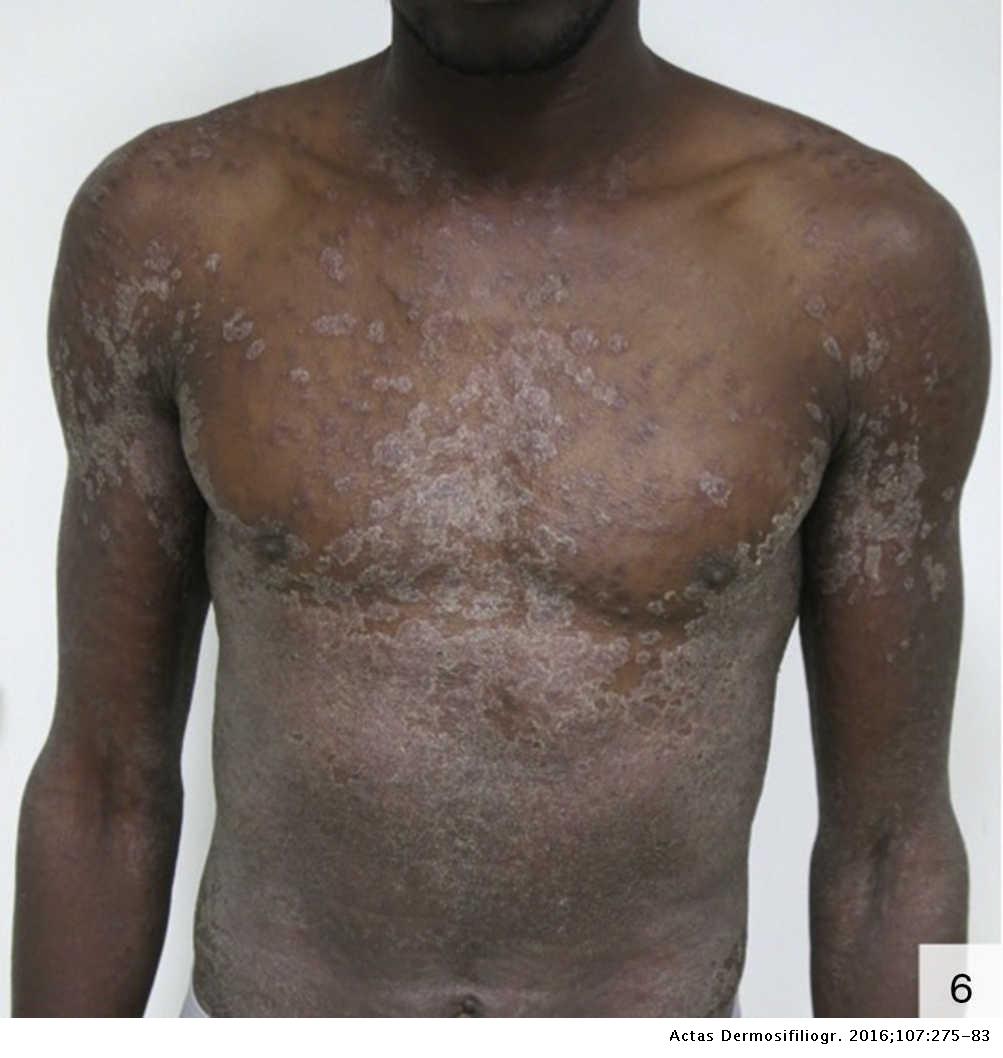

Atypical Cutaneous Manifestations in Syphilis | Actas Dermo-Sifiliográficas

One of the most severe syphilis cases in years – GayIceland

Secondary Syphilis | Basicmedical Key